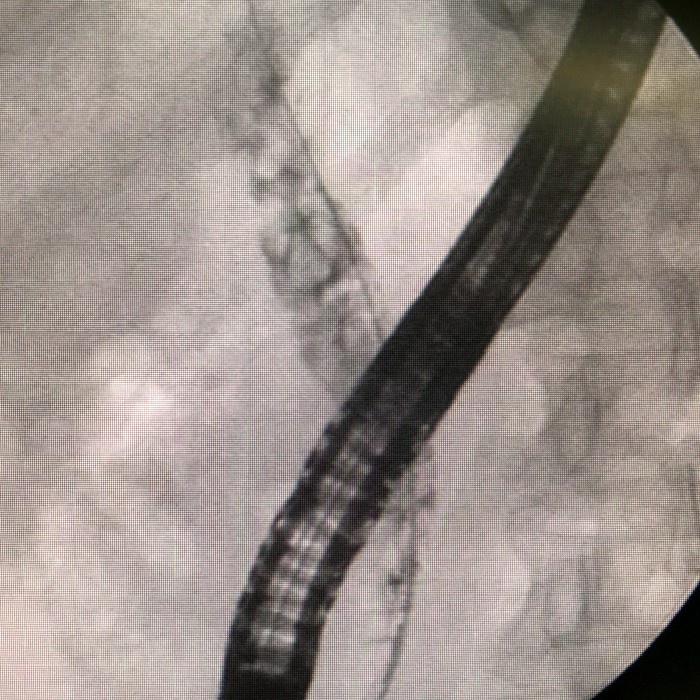

焦奶奶今年82岁了,三周前因腹痛、黄疸、发热入住北京佑安医院肿瘤生物科,经积极药物治疗并完善相关检查后,考虑胆总管结石、胆管梗阻,遂于9月20日行第一次十二指肠镜,胆总管成功插管后见大量脓液流出,造影提示多发结石。考虑梗阻性化脓性胆管炎,遂决定放置塑料支架和鼻胆管先行通畅引流。术后患者感染控制,各项临床、实验室指标明显改善。10月9日拔除鼻胆管和塑料支架后,行十二指肠乳头括约肌切开,取石球囊反复清扫,结果竟然取出大小不等的结石四十余枚,以胆固醇结石为主,其他包括胆色素结石及混合性结石等。

据北京佑安医院消化中心内镜室主任张月宁介绍,胆结石在临床上十分常见,包括胆囊结石、胆管结石(肝内胆管结石、肝总管结石、胆总管结石等)。胆结石引起腹痛、黄疸、发热等症状则称为“胆石症”。目前内镜下逆行胰胆管造影术(ERCP)是胆总管结石的首选治疗手段,而胆囊结石、肝内胆管结石则仍需腹腔镜等解决。在胆结石中,胆固醇结石含胆固醇成分90%以上,质地坚硬、X线平片多不显影。此类结石单发者居多,这例患者共取出以胆固醇结石为主的胆管结石四十余枚,在临床实践中十分少见。此例复杂ERCP术的成功完成,是佑安医院消化内镜技术的又一个标志。